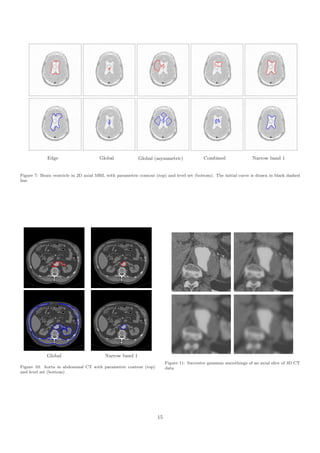

Fig. 7 shows segmentation results of the brain ventricle

in a 2D axial MRI (Magnetic Resonance Imaging) slice.               only the implicit method was tested on this dataset. In

As it is the case with many medical datasets, the partially         order to keep a critical eye on our approach, we draw the

blurred boundaries between ventricle and gray matter                attention on its equivalence with the Chan-Vese model on

prevent the extraction of reliable edges in places. For the         this particular image. The background is not uniform but

edge-based model, we could not find a suitable balloon               still significantly darker than the target object. Thus, the

weight α and gradient scale s preventing the contour from           classical region speed manages to make the front stabilize

being trapped in spurious noisy edges inside the shape              on the actual boundaries. Fig. 8 depicts the typical case

while stopping on the actual boundaries. As regards                 in which there is no particular benefit in using the narrow

combined and symmetric global approaches (see columns               band region energy.

2 and 4), the contour did not manage to grow, as inner and

outer average intensities were not sufficiently different.                 In fig. 9 and 10, we illustrate the recovery of the kidney

Setting λ to 0.9, we decrease the significance of inner              and aorta inner walls, respectively, in 2D CT (Computed

deviation to the benefit of outer deviation, consequently            Tomography) data. The global region energy makes the

allowing the contour to grow. As depicted in column 3,              contour leak outside the target object, into neighboring